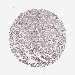

UROTHELIAL CANCER - Protein expressioni

A mouse-over function shows sample information and annotation data. Click on an image to view it in a full screen mode. Samples can be filtered based on level of antibody staining by selecting one or several of the following categories: high, medium, low and not detected. The assay and annotation is described here.

Note that samples used for immunohistochemistry by the Human Protein Atlas do not correspond to samples in the TCGA dataset.

Antibody stainingi

Antibody staining in the annotated cell types in the current human tissue is reported as not detected, low, medium, or high, based on conventional immunohistochemistry profiling in selected tissues. This score is based on the combination of the staining intensity and fraction of stained cells.

Each image is clickable and will lead to virtual microscopy that enables deeper exploration of all samples and also displays staining intensity scores, fraction scores and subcellular localization as well as patient and tissue information for each sample.

Antibody HPA042268

Staining

High

Medium

Low

Not detected

Intensity

Strong

Moderate

Weak

Negative

Quantity

>75%

75%-25%

<25%

None

Location

Urothelial carcinoma, High grade

Urothelial carcinoma, NOS

Urothelial carcinoma, Low grade